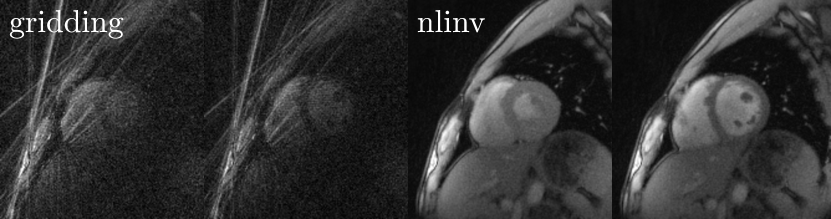

Figure 10: Non-iterative (gridding) and non-linear inversion (nlinv) reconstruction of short-axis view of a healthy human heart at a temporal resolution of 33ms.

Figure 10 shows the difference between a non-iterative image reconstruction method and the non-linear inversion algorithm described in this work. While the extreme radial undersampling causes severe streaking artefacts, the iterative algorithm is capable of reconstruction high-quality images.